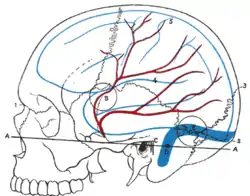

Relations of the brain and middle meningeal artery to the surface of the skull. 1. Nasion. 2. Inion. 3. Lambda. 4. Lateral cerebral fissure. 5. Central sulcus. AA. Reid's base line. B. Point for trephining the anterior branch of the middle meningeal artery. C. Suprameatal triangle. D. Sigmoid bend of the transverse sinus. E. Point for trephining over the straight portion of the transverse sinus, exposing dura mater of both cerebrum and cerebellum. Outline of cerebral hemisphere indicated in blue; course of middle meningeal artery in red. | |